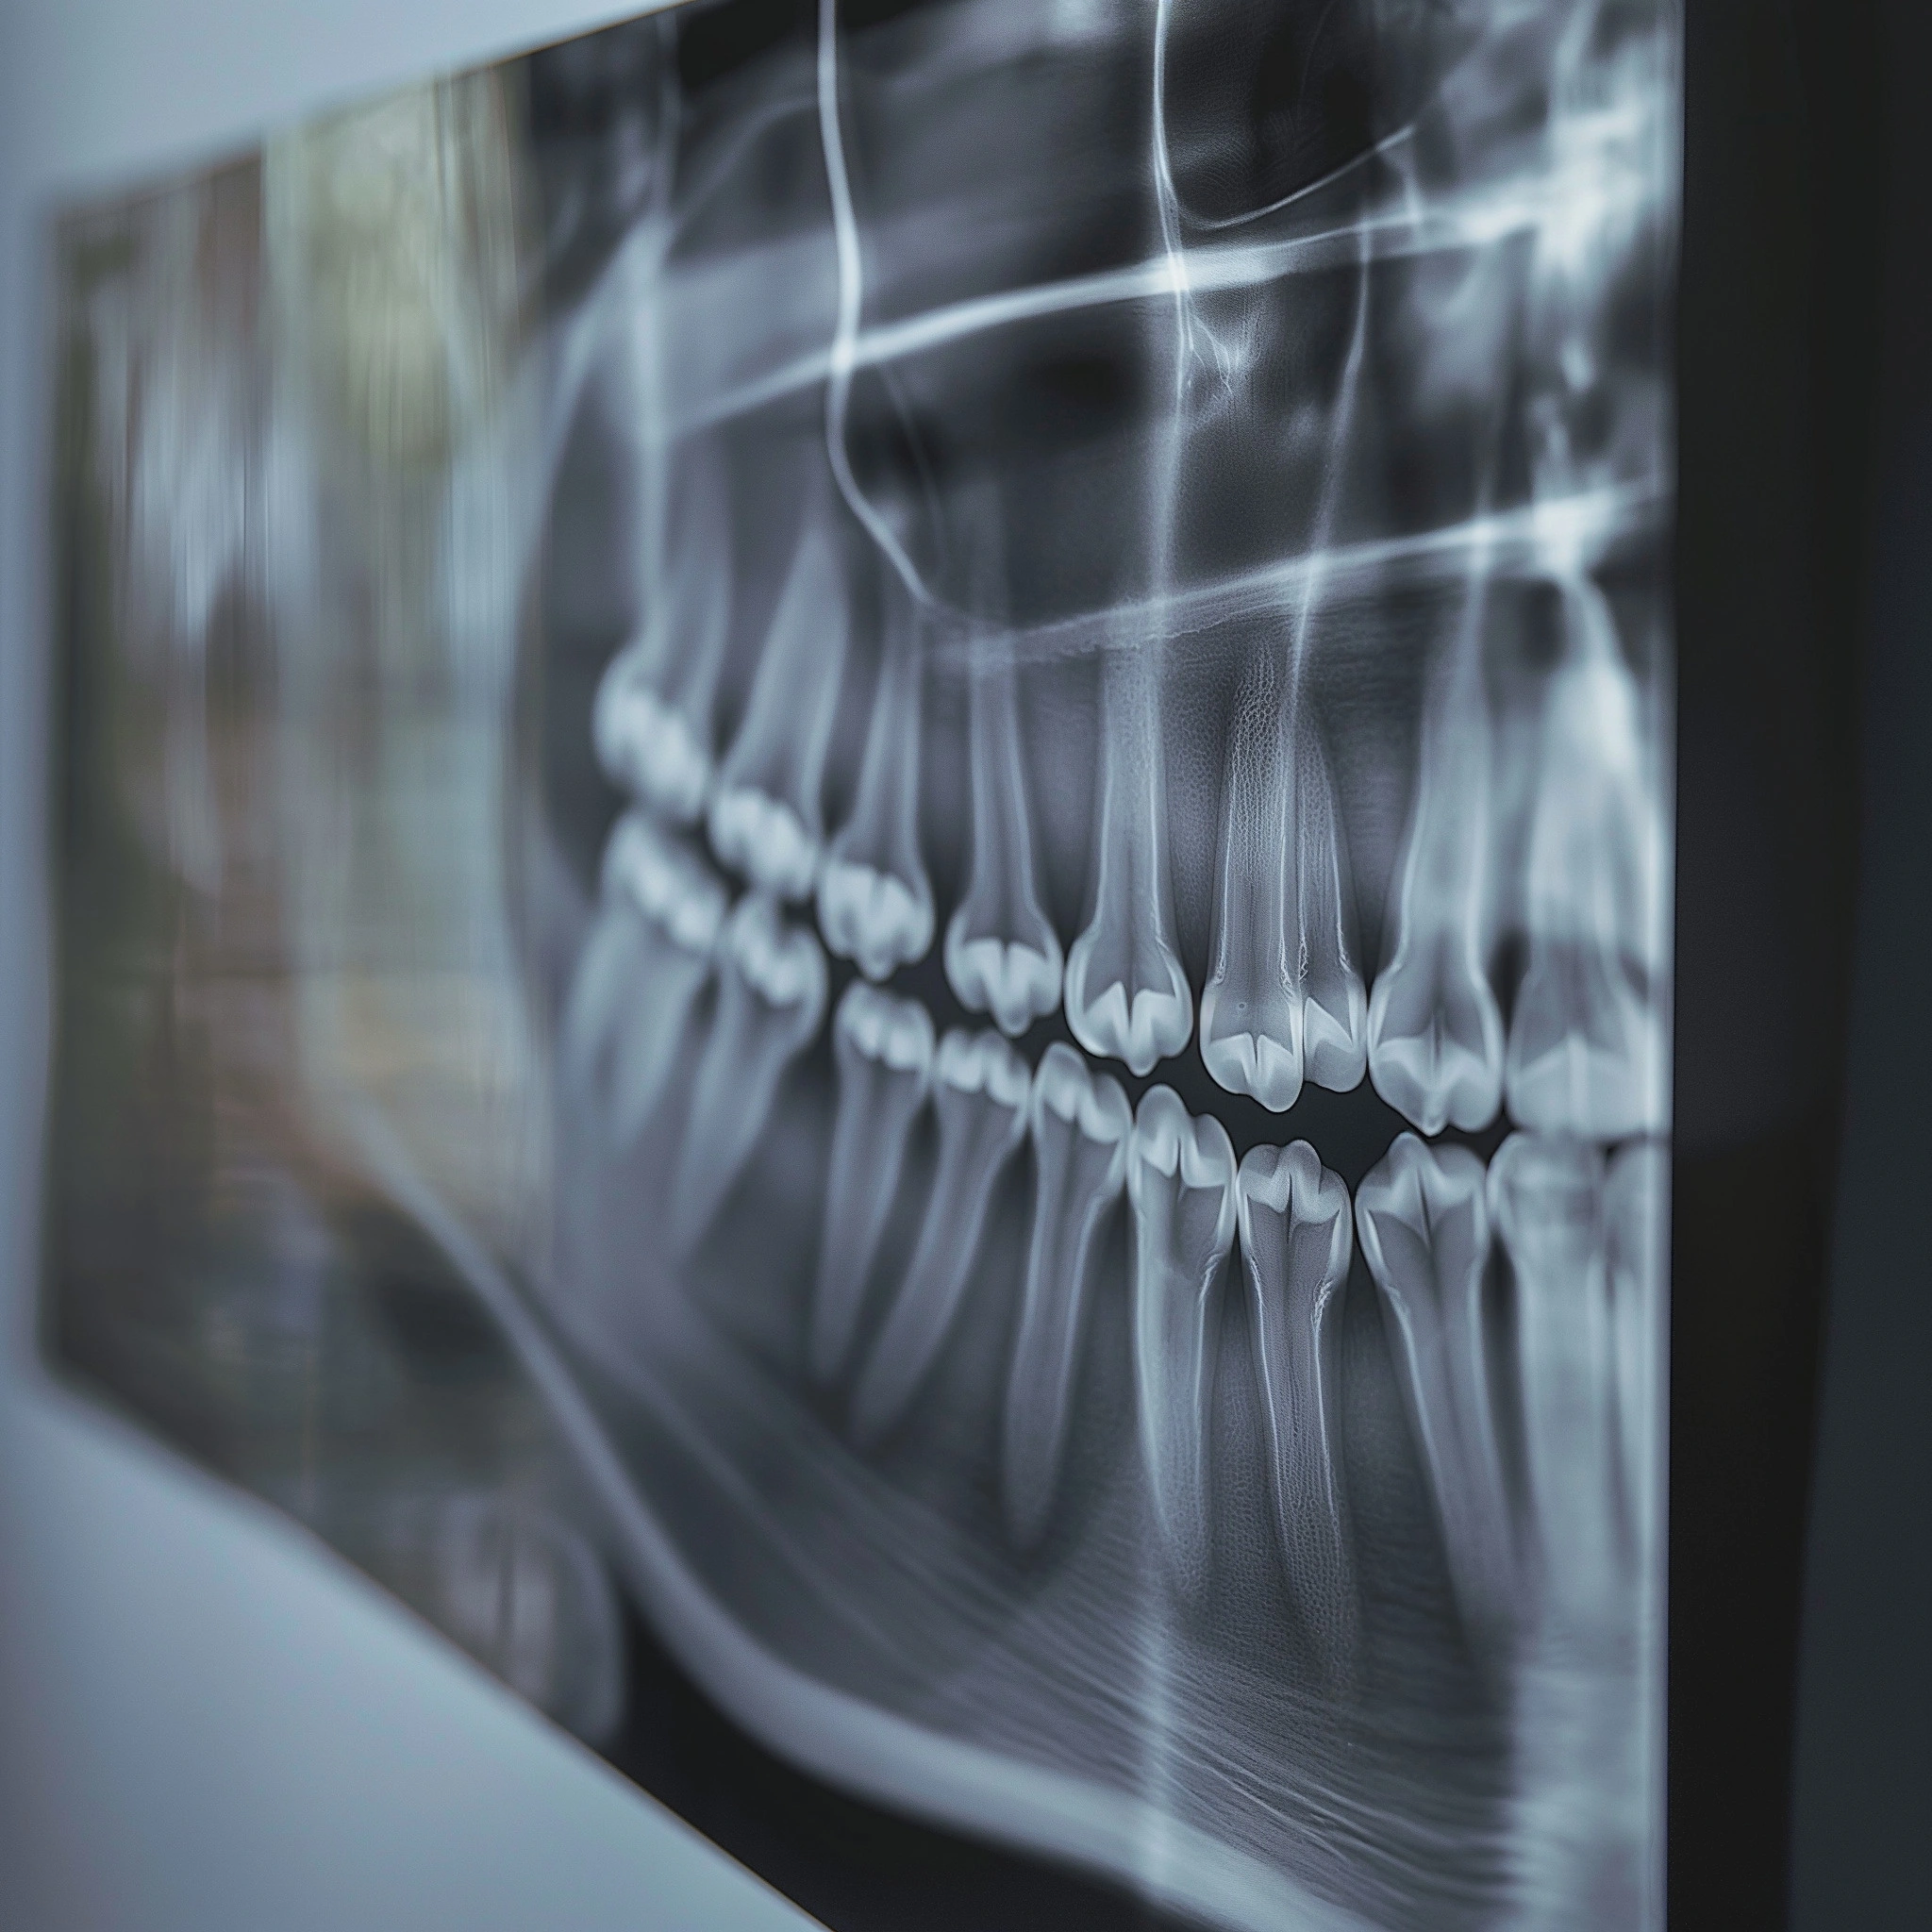

Před zákrokem provedeme důkladné vyšetření včetně rentgenového snímku k posouzení polohy zubu a plánování optimálního postupu. Zákrok probíhá v lokální anestezii, která zajistí bezbolestný průběh.